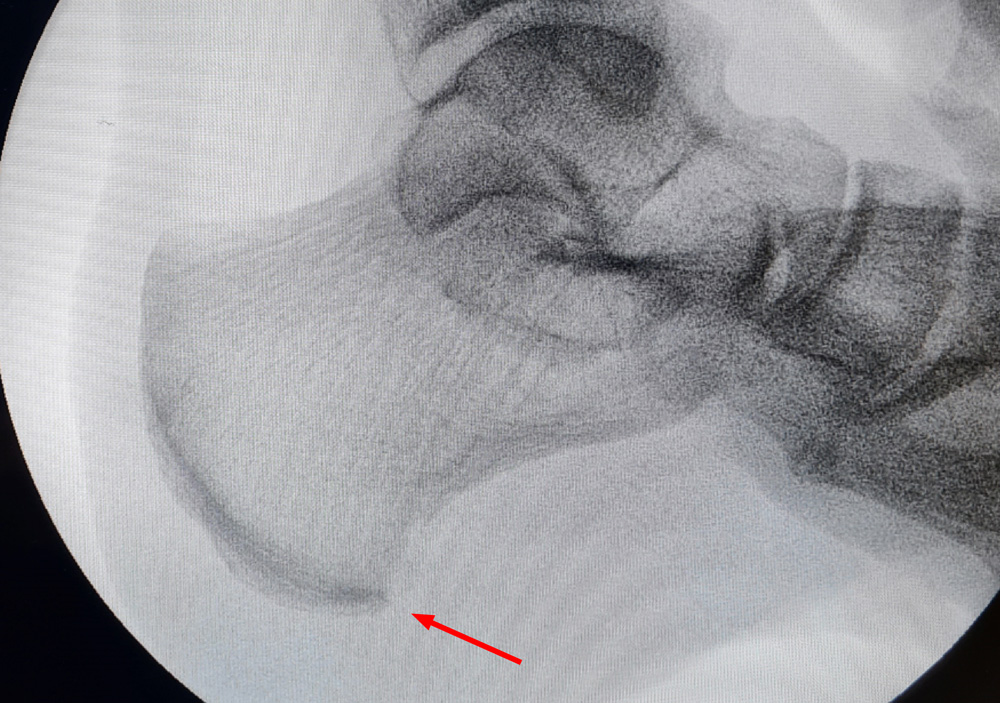

Beispiel 2:

Ein spornreicher Fuß

Unterer Fersensporn

Gelber Pfeil: Der eigentliche Fersensporn ist der untere

Roter Pfeil: Oberer Fersensporn

Grüner Pfeil: Ein zusätzlicher kleiner unterer Fersensporn